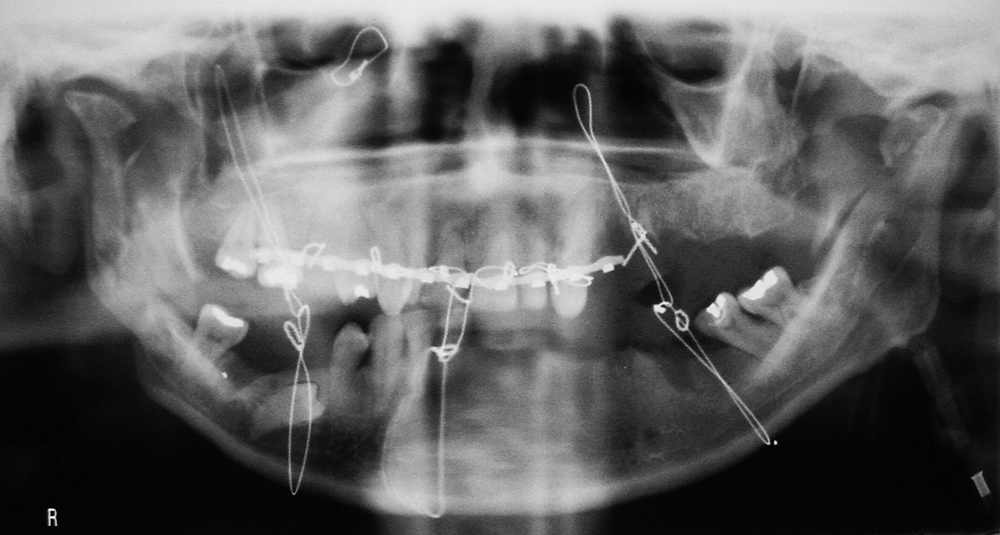

Mandibular and maxillary wiring |

The mandibular and maxillary wires were placed to treat the bilateral mandibular fractures. |